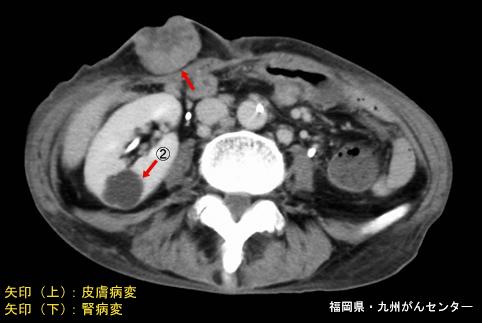

症例提示(所在地,施設名等): 福岡県・ 九州がんセンター

性別 男性

年齢 65-69

部位(臓器別)2つ以上の臓器/

検査方法CT

病変の最大径(ミリ)40以上

多発腫瘍(同一臓器)

多重腫瘍(他臓器)